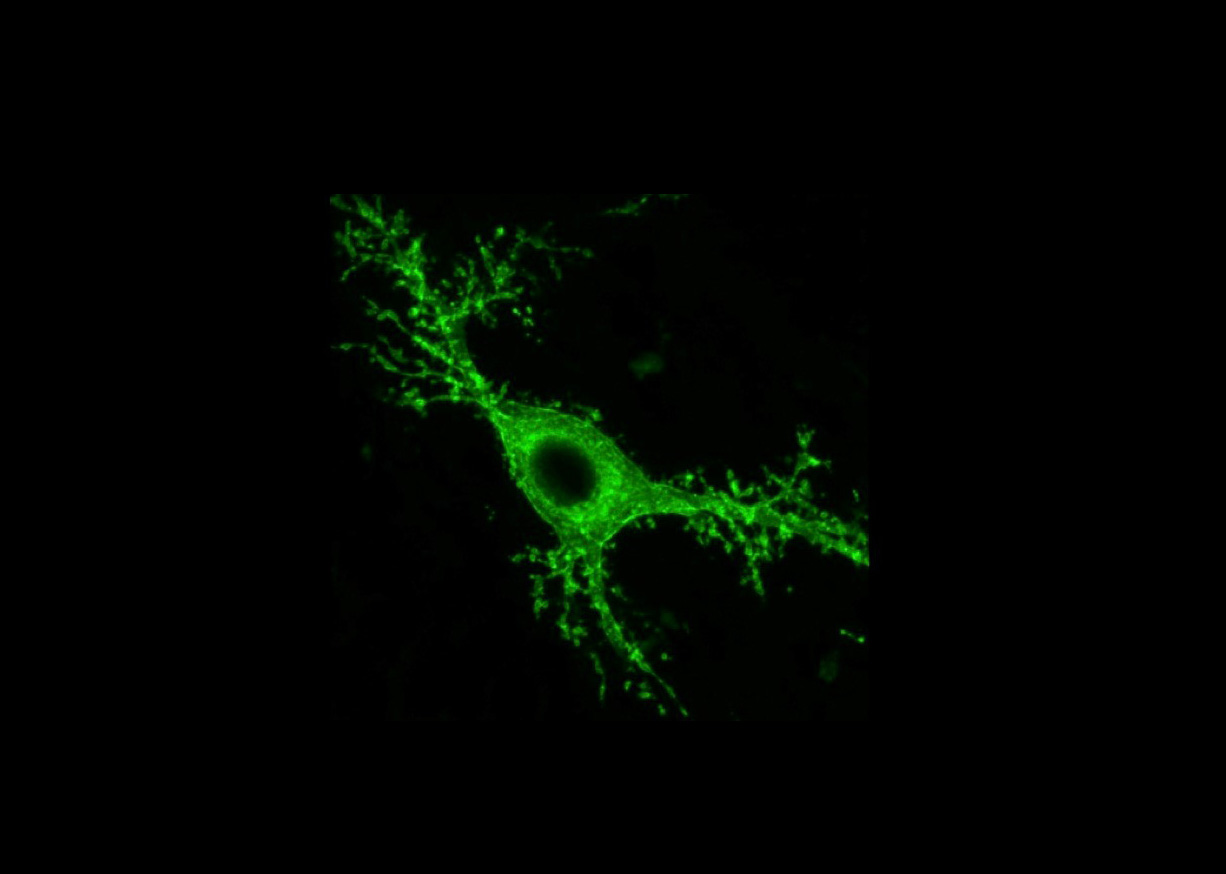

Mossy cells, named for the dense moss-like protrusions that cover their surface, are located in the hippocampus, a brain area that is known to play key roles in memory. Loss of mossy cells is associated with TLE, but it is unknown what role that plays in the disease. Using state-of-the-art tools, Ivan Soltesz, Ph.D., professor of neurosurgery and neurosciences at Stanford University, Palo Alto, California, and his team were able to turn mossy cells on and off to track their effects in a mouse model of epilepsy.